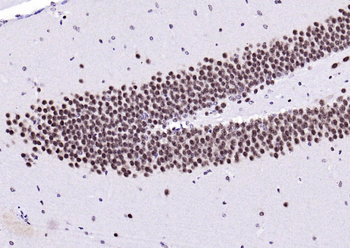

IHC staining of FFPE human brain with Ubiquitin antibody (clone PBQN-1). Required HIER: boil tissue sections in pH9 10mM Tris with 1mM EDTA for 10-20 min followed by cooling at RT for 20 min.